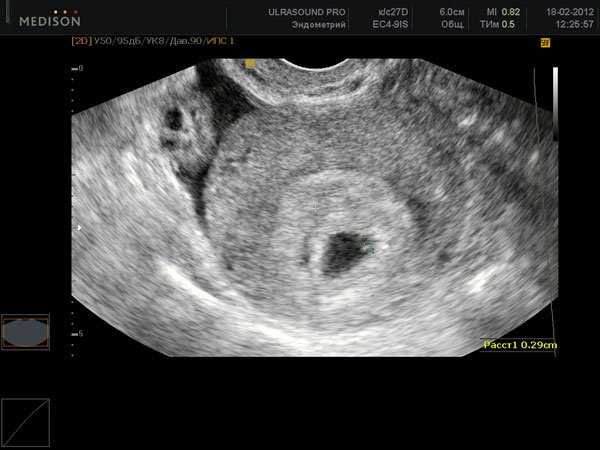

Если ответ положительный, то не нужно сразу бежать на УЗИ, так как зародыш еще маленький и его нельзя отличить от полипов слизистой оболочки. Но на какой день задержки УЗИ покажет подтверждение беременности? Если она есть, то хороший специалист это может подтвердить через 6 дней со дня задержки. Это приблизительно через 3 недели после зачатия.